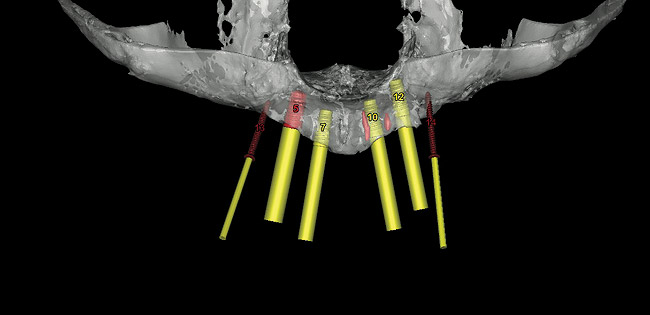

These patients were tested for two different treatment options; either a bar-supported overdenture requiring four implants in the first premolar area or anterior to the bicuspids, or a "simple fixed prosthesis" anchored by six implants placed bilaterally from first-molar-to-first-molar regions. When a flapless, guided surgery was contemplated, the investigators determined that based on the available maxillary bone, 70% of patients (28 implants) could undergo this treatment modality. Of the 40 patients, 15% could not have any implants placed due to inadequate bone height and width. For "simple fixed prostheses," only 30% (72 implants) of patients presented with adequate bone dimensions permitting a flapless guided placement of six maxillary implants placed symmetrically around their arch in a flapless manner. For the fixed treatment, 18% of patients could not have any implants placed due in insufficient bone dimensions. The authors concluded that advertisement of computer-guided, flapless solutions are "euphoric," and tend to overlook patients' individual oral and anatomic conditions. They felt that guided surgery does provide better control of implant placement leading to higher predictability of treatment outcomes. In a study where the accuracy of virtually placed implants and actual positions in a cadaver model were compared, Petterson et al7 found significant differences related to deviations in hex, apex, and depth of the two placements. Without the preparedness to temper treatment expectations or plan on delivery of the pre-fabricated "final" prosthesis immediately after surgery, these types of studies should lead clinicians to proceed with caution in these procedures. The efficacy of an open approach, one requiring a mucoperiosteal flap, may be improved upon with a guided approach in cases where severe ridge-resorption is treated, and may be more predictably handled using this technology. A bone-supported template, affixed to the alveolar ridge with fixation screws, can be fabricated with numerous software package and stereolithography (Figure 8 and Figure 9). A full-thickness flap is elevated, exposing the resorbed alveolar ridge (Figure 10). Using osseous fixation screws, the template is stabilized to the ridge, preventing any movement during osteotomy preparation (Figure 11). Using a sleeve-in-sleeve, manufacturer-specific surgical armamentarium, implants can be placed in the optimal positions, where the maximum amount of initial bone to implant contact is achieved. The anticipated bone augmentation procedures can then be performed, which is not possible with a closed procedure (Figure 12). The flaps are subsequently closed, allowing for the patient to wear any transitional, soft-relined denture. The surgical guide can also serve an important function at the time of implant uncovering. The location of the implants beneath the healed mucosa can be determined by seating the guide and sounding with a 30-gauge anesthetic needle. Using a tissue punch, the implants can be uncovered without flap elevation; the cover screws can be removed and the appropriately sized healing abutments can be placed (Figure 13). From this point forward, traditional prosthetic steps are followed to fabricate an implant-supported/retained overdenture.

Figure 8  Virtual implant placement and fixation screws.

Figure 8

Figure 9: Stereolithic model of edentulous maxilla and bone-supported guided surgery stent.

Figure 9